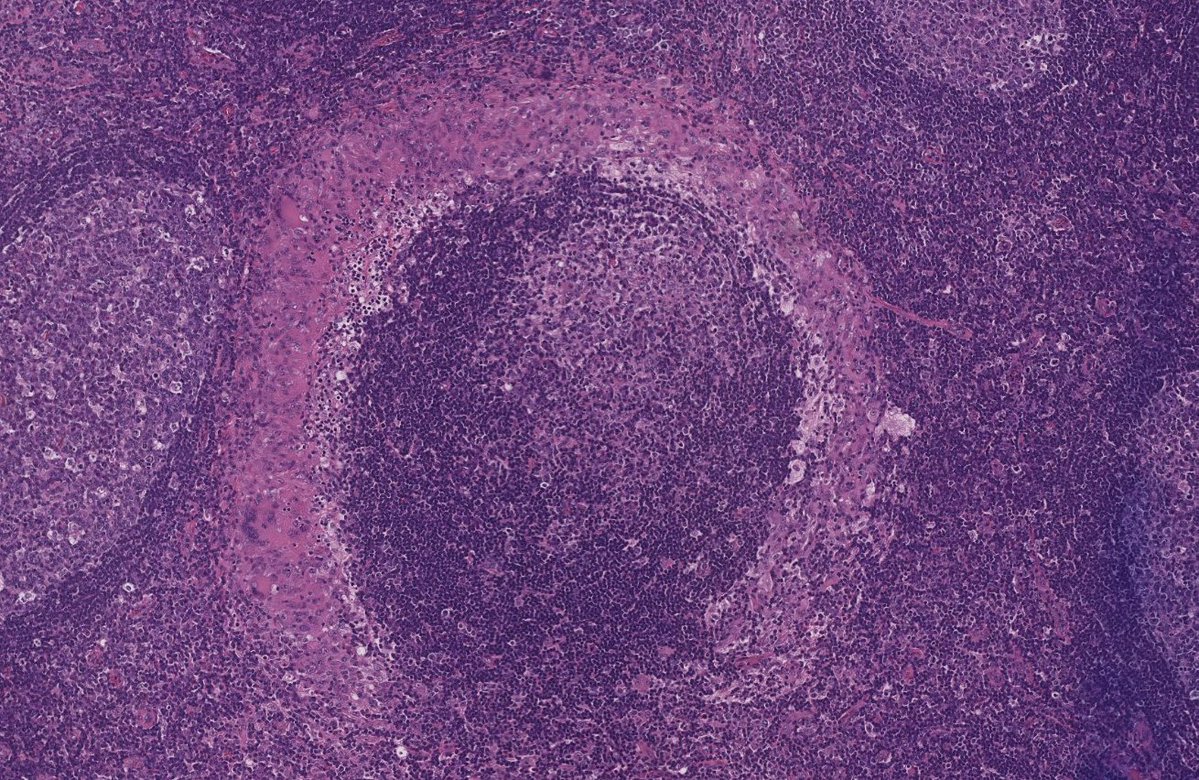

Perifollicular ring-like granuloma is a nonspecific morphologic feature that should prompt consideration of IgG4-related disease, particularly in lymph nodes with plasmacytosis #Hemepath #Surgpath #PathX #PathTwitter #MedEd #SoMe